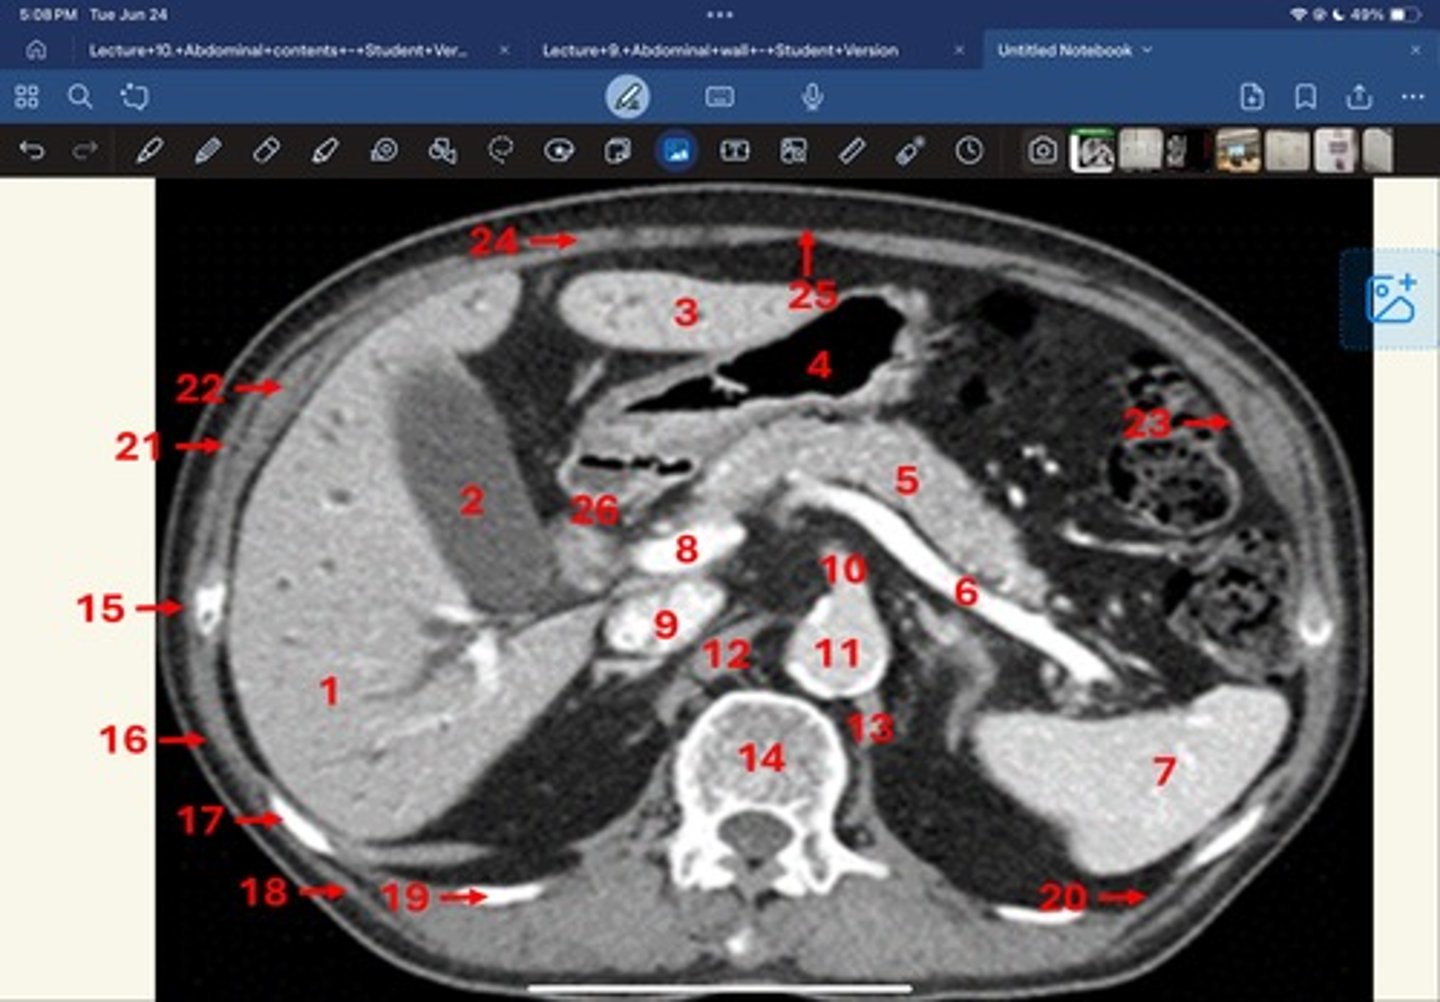

Right lobe of liver

What is 1

Gallbladder

What is 2

Left lobe of liver

What is 3

Stomach, pylorus

What is 4

Pancreas

What's 5

Splenic vein

What's 6

Spleen

What's 7

superior mesenteric vein

What's 8

Inferior vena cava

What's 9